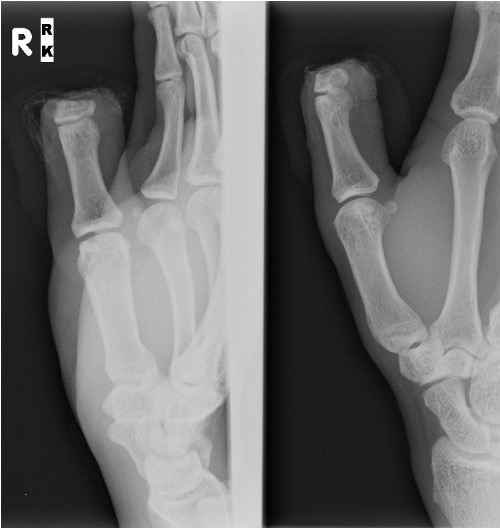

![]()

Technique

Ulnar sided artery larger

Need to adduct shoulder / internally rotate arm

Can fuse IPJ